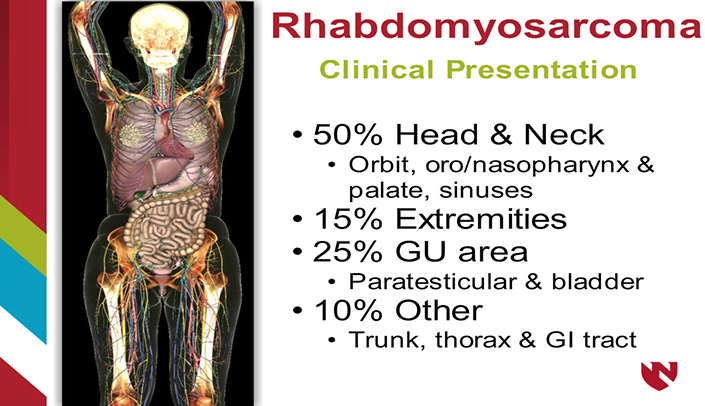

PPT - Pediatric Head And Neck Malignancies PowerPoint Presentation

www.slideserve.com

www.slideserve.com

rhabdomyosarcoma neck presentation pediatric head malignancies ppt powerpoint dna amplification gene cases

Rhabdomyosarcoma: A Musculoskeletal Pathology Case Study | E-Gallery

www.unmc.edu

www.unmc.edu

rhabdomyosarcoma musculoskeletal